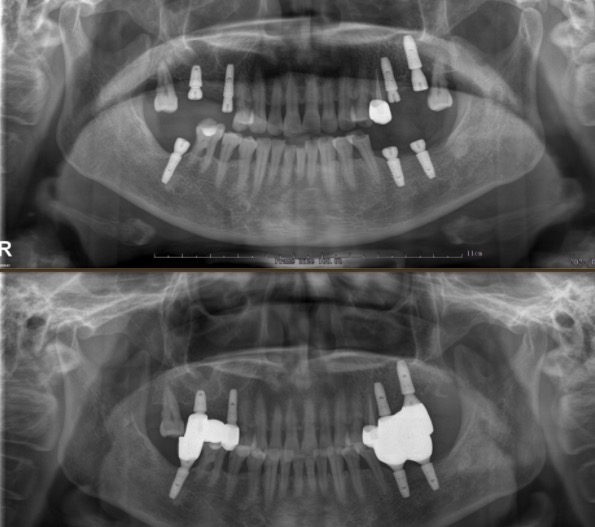

种植牙、部分牙列缺损、全口牙列缺损、即刻种植牙、微创种植牙、疑难种植牙等。

凌锷峰现任牙博士口腔上海区域种植院长,从事口腔诊疗工作十余年,拥有着比较丰富的口腔诊疗工作经验,尤其擅长于种植牙领域,对于各种种植牙疑难杂症都能较好的处理,种牙技术也得到了患者的认可!

诊疗项目 : 种植牙,单颗种植,多颗种植,半口种植,全口种植,即刻种植牙